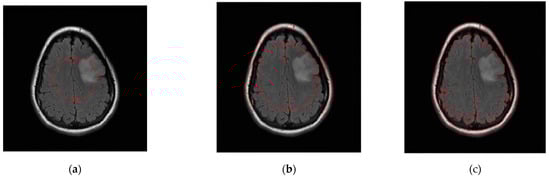

The level set initialization is required to segment the image by the CV model, and the average gray values c1 and c2 of the foreground and background are initially estimated according to the initialized level set. Then, each point on the level set is updated through the evolution equation. If the gray value of the current point is close to the gray average value of the foreground, the value of the corresponding level set of this point increases, otherwise it decreases. In CT and MRI images, the grayscale difference between brain tumors and background images is very small, and the boundaries are blurred. It is difficult to achieve satisfactory segmentation when directly applying the CV model to cross-sectional images for brain tumor detection. As shown in Figure 6, the CV model fails to converge to the location of the brain tumor.

Figure 6.

Brain tumor segment by CV model under different numbers of iterations. (a) 50 iterations. (b) 300 iterations. (c) 1000 iterations.